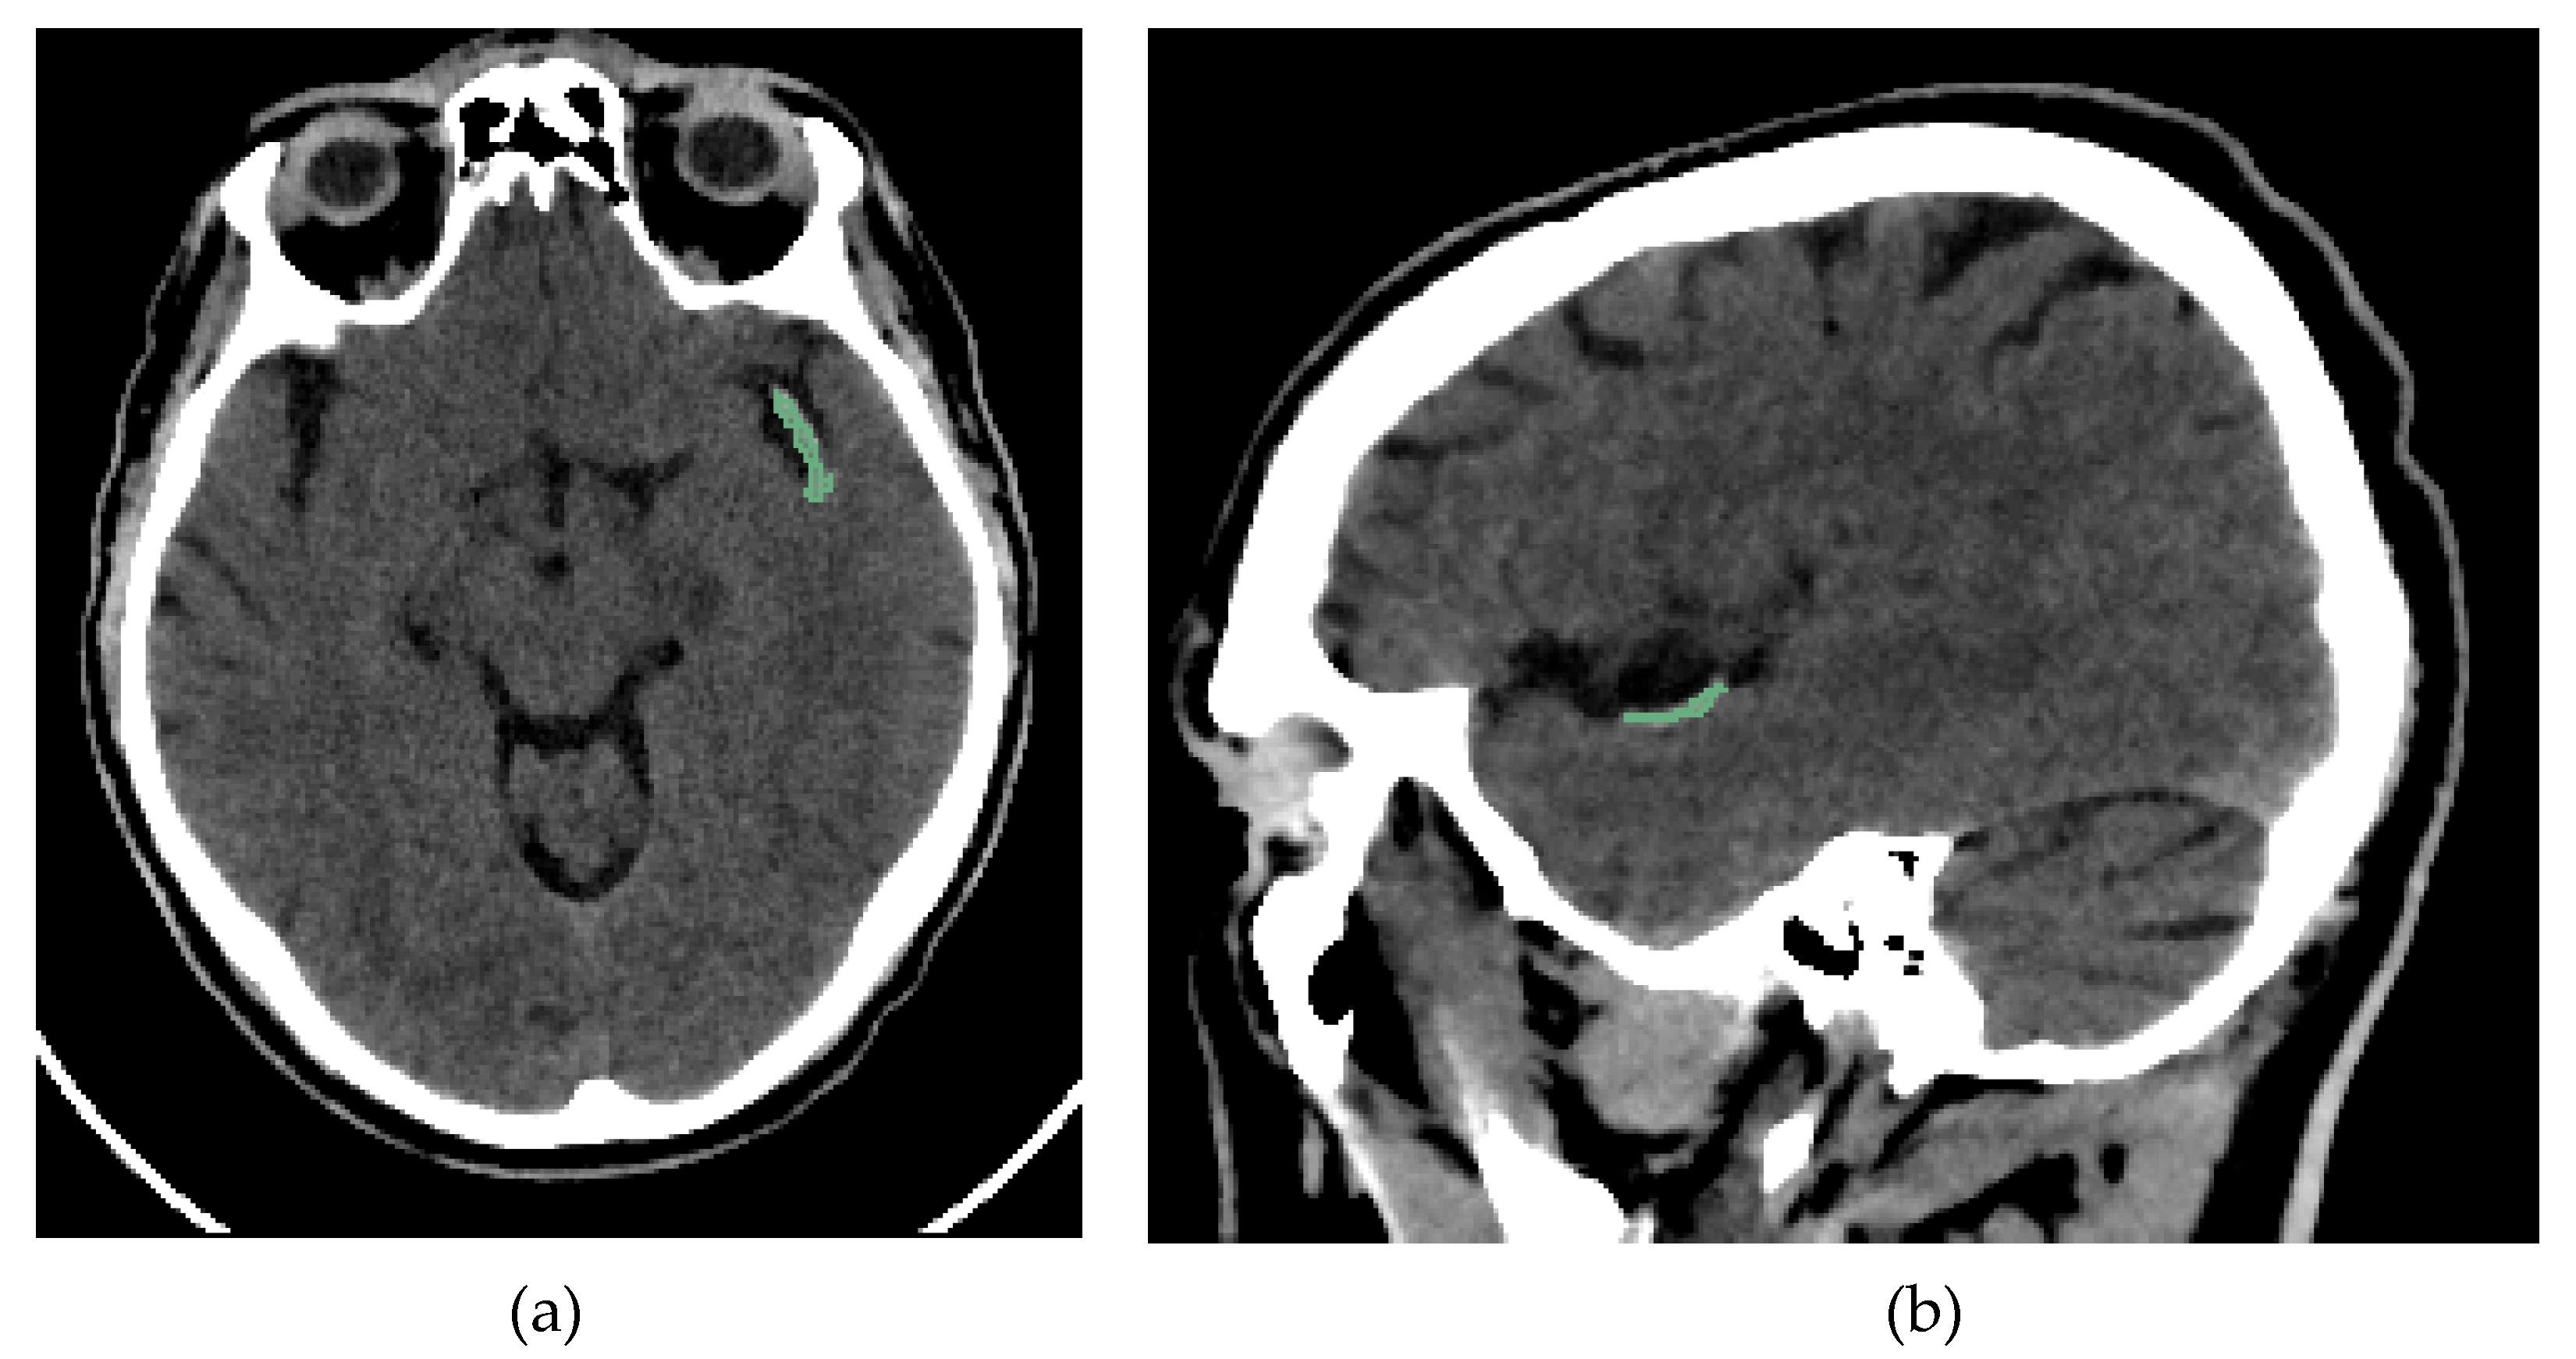

Two interventional neuroradiologists and a radiology resident who had undergone specialized training performed semi-automated segmentation of each thrombus. The segmentation was conducted using the open-access software 3D Slicer (version 5.2.2, Massachusetts, USA) [17]. The software includes a segmentation tool (Level Tracing tool) that enables semi-automatic segmentation based on automatic edge detection. The region of interest segmented was the clot visible on NCCT in patients with AIS (Figure 2). Segmentation was performed in all three spatial planes (Figure 3). The window width and center were set to 100 and 50 HU, respectively.

Figure 2. Brain NCCT of the same patient as in Figure 1, with the thrombus segmented. The segmentation was performed using the “Level Tracing” tool of 3D Slicer. (a) Axial NCCT with thrombus segmented. (b) Sagittal NCCT of the same patient with the thrombus segmented.